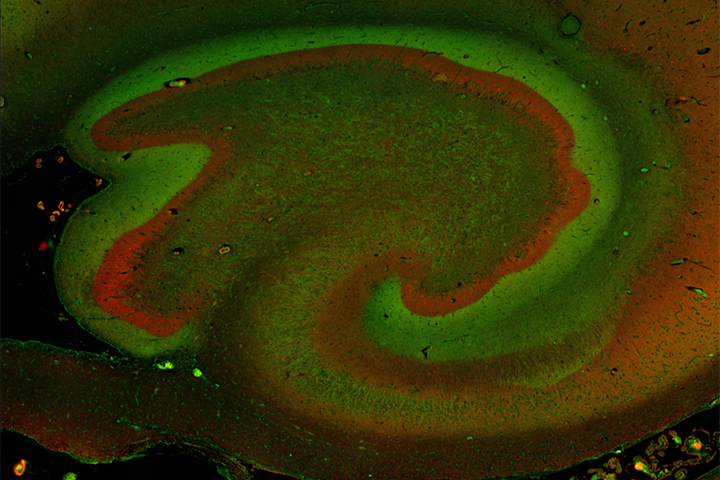

D’après la Fondation française pour la recherche sur l’épilepsie (FFRE), la maladie touche 650 000 personnes en France, la forme la plus fréquente chez l’adulte étant l’épilepsie du lobe temporal. La plupart des patients sont traités au moyen de médicaments antiépileptiques, qui s’avèrent cependant inefficaces dans environ 30 % des cas (pharmacorésistance). À l’heure actuelle, la seule solution consiste alors à réaliser une intervention chirurgicale (résection) pour retirer la partie du cerveau à l’origine des crises – incluant généralement l’hippocampe, situé dans le lobe temporal. Une méthode souvent efficace, mais invasive et susceptible d’altérer des fonctions cognitives telles que la mémoire ou l’orientation dans l’espace.

Christophe Mulle, directeur de recherche au CNRS, responsable d’équipe à l’IINS, et Valérie Crépel, directrice de recherche à l’Inserm, ont exploré une autre voie possible de traitement, à travers un projet collaboratif amorcé en 2011. À l’inverse des approches traditionnelles, leur idée était de s’attaquer à une cible thérapeutique spécifique, située au sein de l’hippocampe. Son nom : les récepteurs kaïnate.